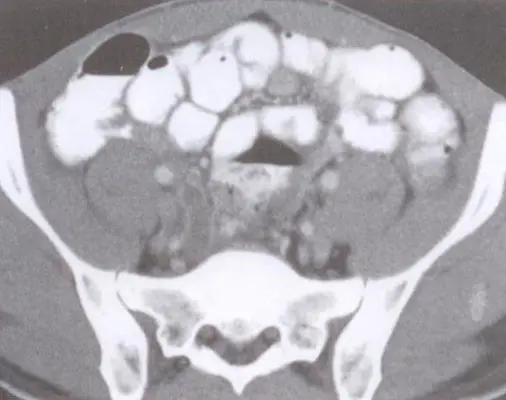

在上述病例中,通过上腹部和下腹部的影像检查,发现了阑尾管径稍增粗,内部存在异常高密度影,这些都是急性阑尾炎的典型表现。及时的影像学诊断对于明确病情、制定治疗计划具有重要意义。

影像检查中提到的双肾见点状高密度影及类圆形低密度影,可以与双肾结石或囊肿有关。这些也是急性感染可能引发的其他问题,需综合考虑病情,进行全面治疗。